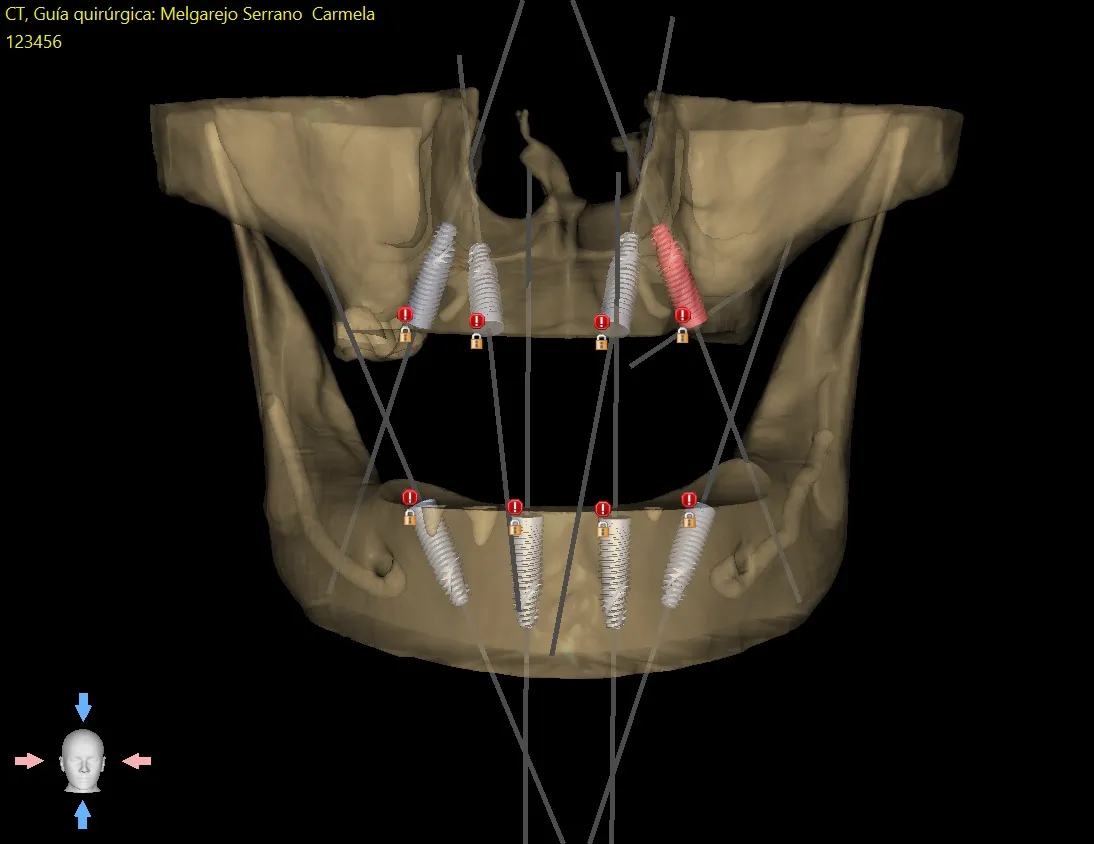

In addition to our expertise in managing severe bone atrophy of the jaws, we also offer different solutions in conventional implantology. We offer everything from single implants to any of the multi-implant options, such as All-on-Six and All-on-Four. All our cases are digitally designed, and the implants are placed using placement guides. This approach provides a whole series of advantages, which we discuss below.

This is the most important advantage. By planning in 3D, the surgeon can "see" through the bone and gum.

- Precision: It eliminates the guesswork and variability of freehand surgery. The implant is placed with submillimetric accuracy, exactly where it was planned.